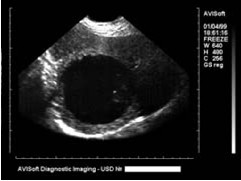

Укажите, для какого заболевания характерны изменения на сонограмме

*киста печени